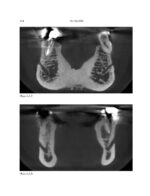

THE MANDIBLE: An Atlas Osteological and Radiological Anatomy 2022

کتاب افست و اطلس رنگی و ارزشمند”THE MANDIBLE: An Atlas Osteological and Radiological Anatomy 2022 ” ویرایش اول